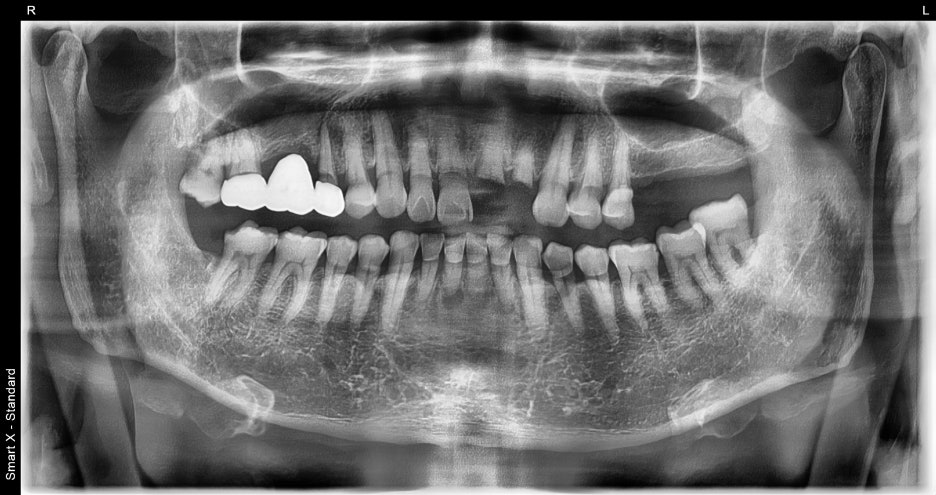

Diagnostic results

As a result of the detailed examination,

Lip and gum lacerations → suturing required

Fracture of the maxillary front teeth and extraction required

Damage to the mandibular front teeth requiring extraction

The overall condition of the gums and alveolar bone was good,

and the result indicated that implant placement was possible.